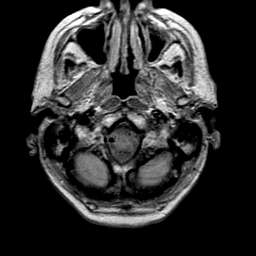

Meningioma, MR Study #1 -- Slice #0

[Home][Help][Clinical] Slice 0